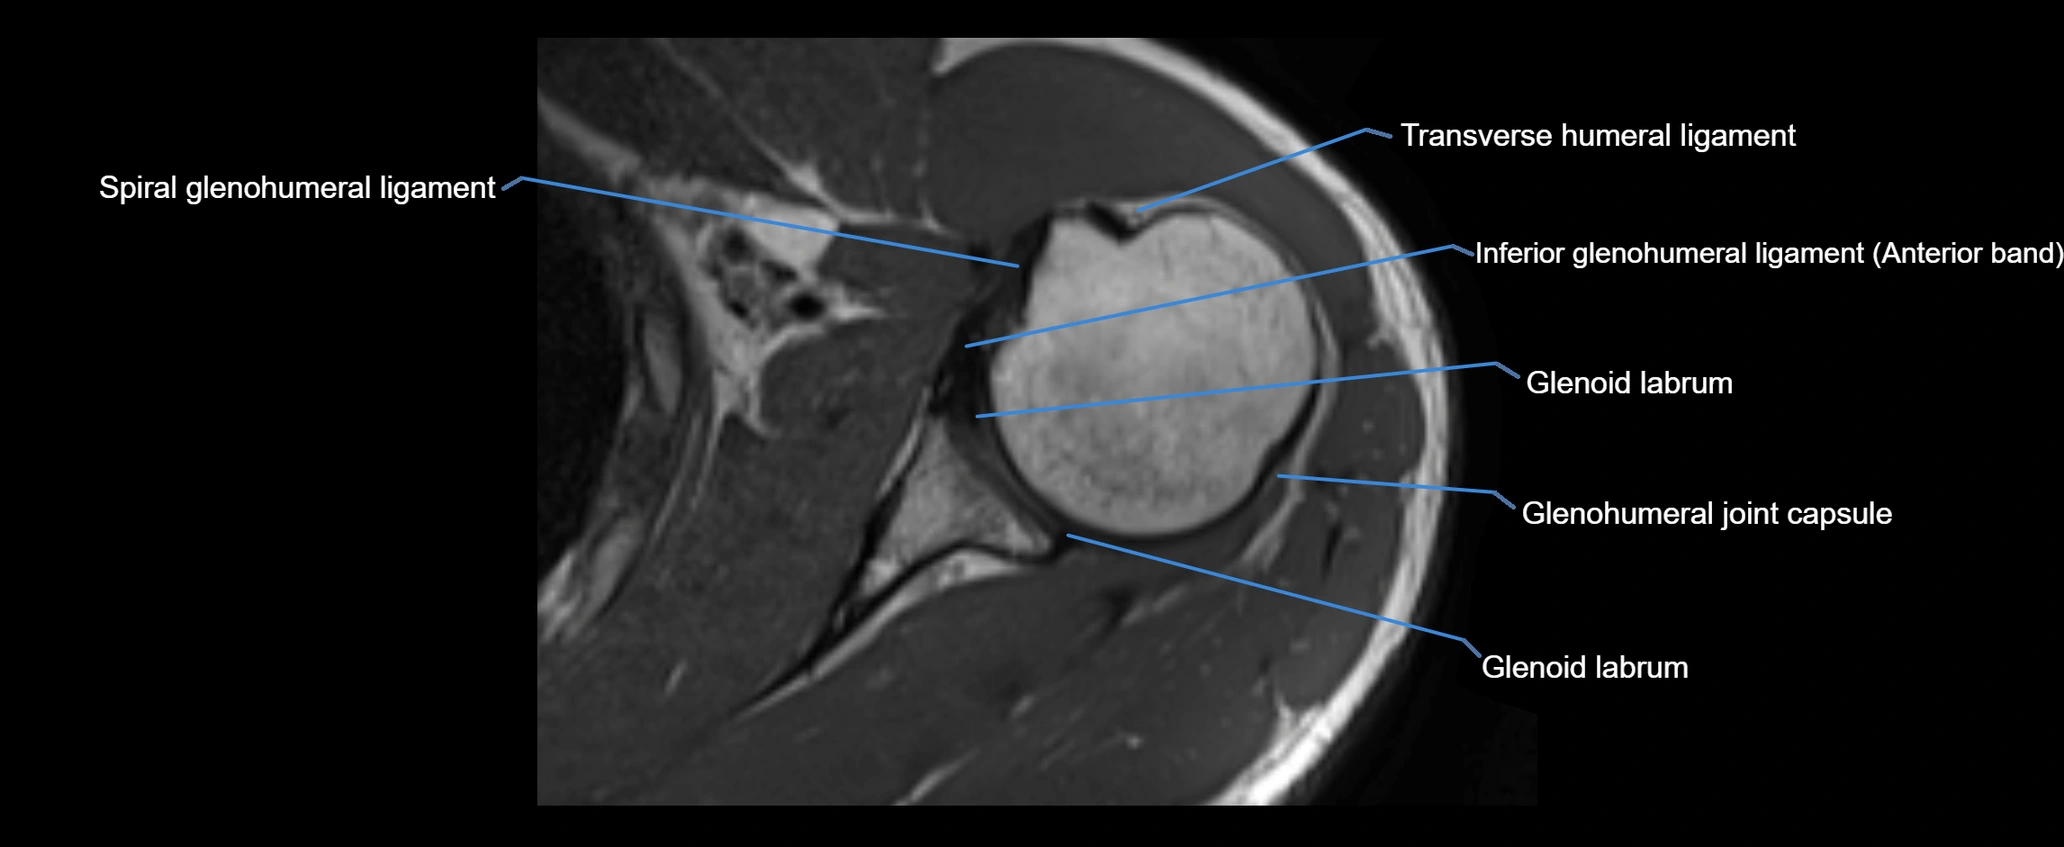

MRI images

image